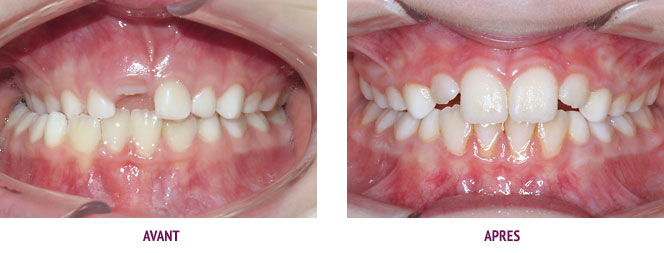

Cas Orthodontie Paris 4 : Alignement et élastiques d’un côté

Le motif de consultation était la mauvaise position de l’incisive supérieure, mais la patiente présentait également un excès de recouvrement incisif (incisives inférieures trop recouvertes par les incisives supérieures) et un décalage des arcades d’avant en arrière de 3 mm à droite (à gauche sur la photo). C’est le décalage des dents qui a été à l’origine des troubles de l’alignement des dents supérieures. Un contact trop fort entre les incisives du haut et du bas peut être à l’origine d’abrasions (usures) des incisives inférieures.

L’orthodontie a permis d’obtenir l’alignement espéré et surtout une occlusion fonctionnelle par nivellement des arcades et le port d’élastiques inter-arcades à droite. Les photos de fin présentées ici ont été prises 3 ans après la fin du traitement et montrent la stabilité. Le traitement a duré un an grâce au sérieux de la patiente.